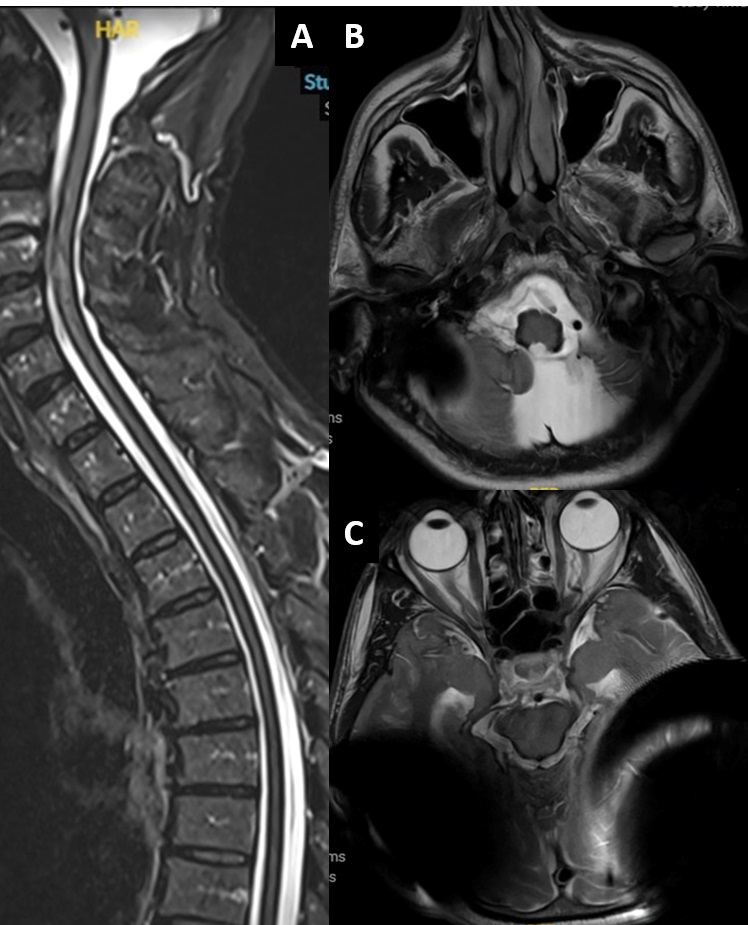

Un patient de 60 ans consulte en 2023 devant l’apparition progressive d’une ataxie depuis 2018, et plus récemment d’une sensation de flou visuel. Dans ses antécédents, on note une surdité neurosensorielle apparue autour de 2009, pour laquelle il a bénéficié de la pose d’implants cochléaires en 2015. Il n’y a pas d’antécédent familial de surdité. Les troubles de la marche, très discrets en 2018, sont nets à présent, avec élargissement du polygone de sustentation et instabilité franche. L’examen retrouve de plus une atteinte de la VIème paire crânienne de façon bilatérale avec strabisme convergent. Dans le cadre du bilan de ces troubles, une IRM cérébrale et médullaire est réalisée (séquences T2), malgré les artéfacts causés par les implants cochléaires.